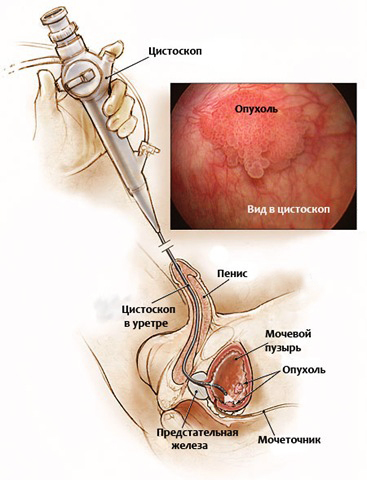

Прежде чем начать лечение рака мочевого пузыря, следует точно диагностировать заболевание. Существует несколько способов диагностирования онкологии:

- цистоскопия;

Еще одна достаточно типичная картина рака мочевого пузыря, видимая при цистоскопии: